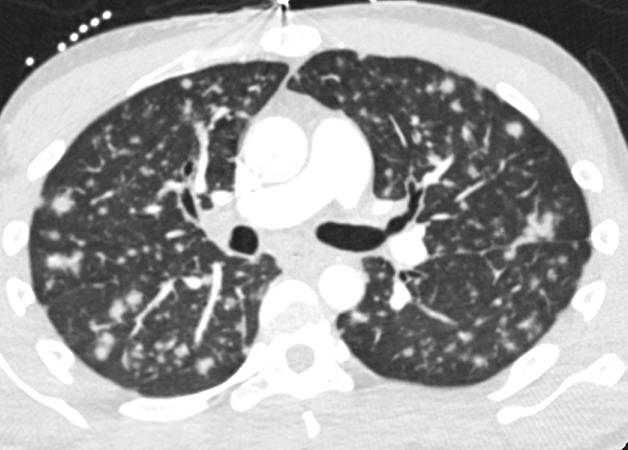

A 30-year-old man with a remote history of HIV/AIDS, subsequently lost to follow up presented with a 3-week history of sore throat and coughing with occasional hemoptysis. Physical exam was normal. Chest CT scan showed innumerable bilateral pulmonary nodules 6-9 mm in size (Figure 1). A transbronchial biopsy of the right lower lobe was performed for further evaluation. Microscopically, there were multiple pieces of unremarkable lung parenchyma with only two pieces involved by a monotonous, low-grade spindle cell proliferation with focal fascicular growth pattern (Figure 2). The lesional process also formed vascular spaces, with some having a “slit-like” appearance containing extravasated red blood cells (Figure 3). Rare cytoplasmic hyaline globules were seen. No organizing pneumonia or granulomas were identified. GMS and AFB special stains were negative for fungi and acid-fast organisms, respectively. Immunohistochemical stains showed that the spindle cell proliferation was positive for D2-40 (Figure 4), ERG (Figure 5), and CD34 (focal and weak), while negative for pan-CK and CD68. The spindle cells were positive for HHV-8 in a nuclear speckled pattern (Figure 6). CMV immunostaining was negative.

Pulmonary involvement by KS can be seen in as many as 6-30% of AIDS patients with cutaneous lesions and in 40-75% of these patients at autopsy. However, pulmonary involvement without cutaneous lesions is quite rare. In this setting, patients present with non-specific respiratory symptoms as the ones described in the case (cough, shortness of breath, hemoptysis). The lungs may be involved at any level with often endobronchial lesions seen as red-purple macules or papules on bronchoscopy. Chest HRCT scan demonstrates peribronchovascular and interlobular septal thickening; bilateral and symmetric ill-defined nodules in a peribronchovascular distribution; and fissural nodularity. The diagnosis of pulmonary KS may be suspected based on the integration of the clinical context and imaging findings, however, histopathologic confirmation is required for diagnosis in an endobronchial or transbronchial biopsy.